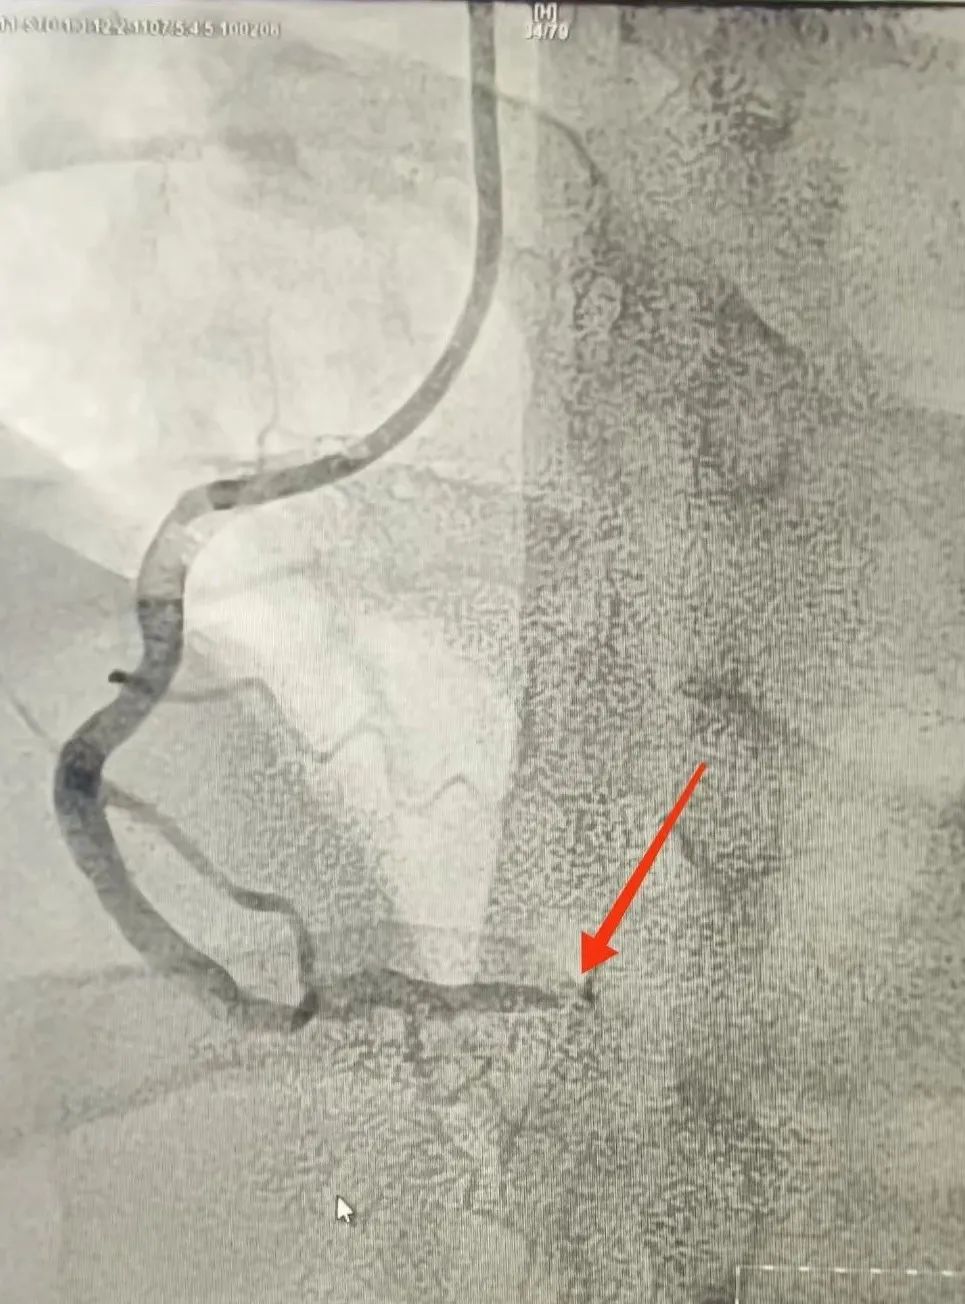

120救護車(che)到(dao)達蘇州九龍醫(yī)院後(hou),龍先(xian)生(sheng)直接被送到(dao)急診搶救室。醫(yī)護人(ren)員(yuan)立即對其完善(shan)相關檢(jian)查。心電(dian)圖提示:窦性心律,1度房室傳(chuan)導(dao)阻滞,II、III、AVF導(dao)聯(lian)ST段擡高(gao);考慮“急性心肌梗死”。情況十分(fēn)緊急,心血筦(guan)內(nei)科(ke)劉廣(guang)安(an)副主(zhu)任醫(yī)師團(tuán)隊(duì)來到(dao)急診搶救室會診,立即啓動(dòng)胸痛中(zhong)心綠色生(sheng)命通(tong)道,直達導(dao)筦(guan)室進(jin)行心髒血運重(zhong)建(jian)!急診“冠狀動(dòng)脈造(zao)影CAG術(shù)”提示:RCA遠(yuǎn)段完全閉塞,血流TIMI 0級;LAD狹窄30%,LCX遠(yuǎn)段狹窄40%。鑒于(yu)患者年(nian)紀輕且病情急,專(zhuan)傢(jia)團(tuán)隊(duì)決定爲(wei)其采用(yong)藥物(wù)球囊PTCA治療。藥物(wù)球囊手術(shù)通(tong)過(guo)向病變血筦(guan)部(bu)位輸(shu)送藥物(wù),達到(dao)擴張血筦(guan)、抑製(zhi)血筦(guan)再狹窄的(de)效果。這種手術(shù)方(fang)式(shi)創傷小(xiǎo)、恢複快,适郃(he)年(nian)輕患者咊(he)需要避免長(zhang)期支架植入的(de)患者。

術(shù)前(qian)

術(shù)後(hou)